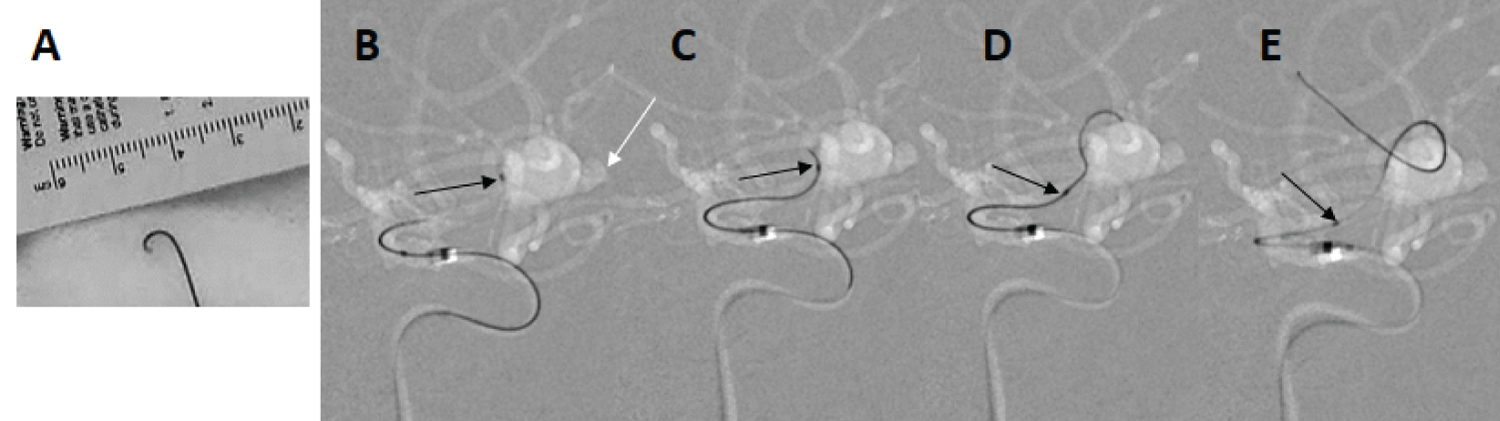

In ten cases, an intra-aneurysmal insertion technique was not necessary; in the seven cases in which this technique was used, only a minor catheter kickback phenomenon was observed during microwire (CHIKAI 315 cm EXC) navigation, and the stress on the aneurysmal wall may be reduced (Figure 1). The stiffness of the tip of the Echelon 10 MicroCatheter seemed to facilitate insertion. In two large aneurysms (> 10 mm), the flexure was released safely after intra-aneurysmal insertion of the microcatheter (Figure 2). Furthermore, in three cases of ruptured aneurysm, SDC guidance was performed without any stress on the aneurysmal wall (Figure 3). In two cases, our attempt to insert the Excelsior XT-17 Microcatheter failed. We then inserted the Echelon 10 MicroCatheter successfully (Figure 4). No thromboembolic events, no vessel injury, and no perforation of the aneurysm occurred during the exchange procedures with the Asahi CHIKAI 315 cm EXC.

Figure 2: A case of the method of releasing the flexure of the catheter in a large aneurysm. The intermediate catheter (double arrows) was inserted near the top of the flexure (A); then the wire (Asahi CHIKAI) was pulled back to the insertion point (dotted arrow; B), and the intermediate catheter and Echelon 10 MicroCatheter (double arrows) were pulled slowly together (C and D). After releasing (white arrow), minimum transposition of the catheter tip occurred (E). The single black arrow in each image points to the tip of the Echelon 10 MicroCatheter. View Figure 2

Intra-aneurysmal navigation is frequently mandatory in the treatment of large and giant aneurysms. In particular, releasing the flexure of the catheter system in giant aneurysms is not easy. Oran, et al. demonstrated the "rapid pull back technique" [14] and Sakamoto, et al. reported the "stent anchor technique" [15] as methods to use when releasing the flexure; these are effective options, but in both techniques, the whole catheter system may exit the distal artery, and recovering the catheter in such a situation is laborious. In our study, it was not easy to release the flexure in the two aneurysms that measured more than 15 mm in diameter, but pulling the intermediate catheter and the Echelon 10 MicroCatheter together resulted in successful release (Figure 2). The Echelon 10 MicroCatheter seemed to be effective for such situations, and this technique was thus considered a useful option. Guidance of the microwire to the target vessel with lower pressure against the aneurysmal wall was possible during intra-aneurysmal navigation (Figure 1).